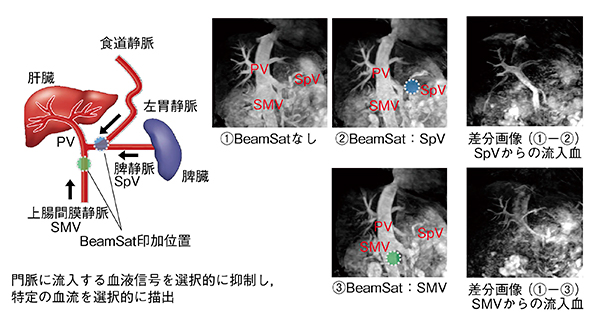

■Selective MRA

“Selective MRA”は,腹部血管の血流信号を選択的に抑制し,腹部血行動態を描出する撮像機能である。局所励起を応用したpencil beam型のプリサチュレーション(以下,“BeamSat”)パルスをMRA撮像に併用し,所望の血流信号を選択的に抑制して,血行動態を把握できる。

撮像手順は,BeamSatパルスで特定血管の信号を抑制し,抑制前後の画像から必要な血行動態を抽出する。圧の上昇,血行遮断がないので通常状態の血行動態が反映され,また,任意の位置を抑制できる。

図2は,本手法の適用例である。BeamSatなしの画像とBeamSatで門脈などの血流を抑制した画像を取得する。この差分をすることで,門脈のみの画像が取得可能である。

図2 Selective MRA:門脈系の血行動態把握